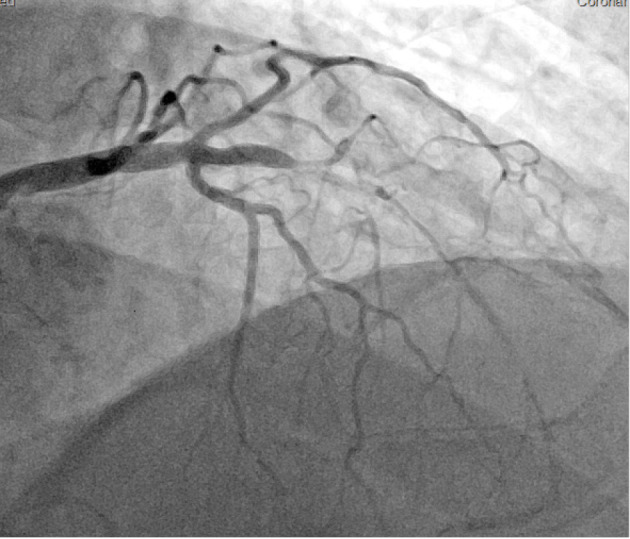

经皮冠状动脉介入治疗(PCI)中严重钙化病变的处理通常与并发症和长期不良结果的高发相关,因为钙化病变导致的冠状动脉支架扩张不理想是不良结果的最强预测因素之一。冲击波血管内碎石术(S-IVL)是一种用于严重钙化冠状动脉狭窄的最佳减积和准备的新技术,但其在急性或延迟优化未扩张支架的疗效方面的数据很少。我们报告了一例66岁男性患者,慢性全闭塞(CTO) PCI术后由于缺乏充分的预扩张和后扩张,导致LAD严重潜在钙化,支架明显扩张不足,其中S-IVL应用,支架扩张良好。S-IVL可考虑用于治疗严重的底层钙化引起的急性和晚期支架扩张不足。

Management of heavily calcified lesions during percutaneous coronary intervention (PCI) is often associated with a high incidence of complications and long-term adverse outcomes as the suboptimal coronary stent expansion due to calcified lesion is one of the strongest predictors of adverse outcomes. Shockwave intravascular lithotripsy (S-IVL) is a new technique used in the optimal debulking and preparation of severely calcified coronary artery stenoses, but there is few data on its efficacy in acute or postponed optimization of underexpanded stents. We report a case of a 66-year-old male patient with severe underlying calcification of LAD and a marked stent underexpansion after PCI of chronic total occlusion (CTO) due to a lack of adequate predilatation and postdilatation, where S-IVL was applied, resulting in excellent stent expansion. S-IVL could be considered for treating acute and late stent underexpansion caused by severe underlying calcification.